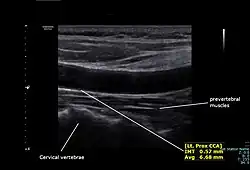

The average diameters of the common carotids in adult males and females are 6.5 mm and 6.1 mm respectively.[6]

The condition and health of the common carotid arteries is usually evaluated using Doppler ultrasound, CT angiography or phase contrast magnetic resonance imaging (PC-MRI).

Typically, blood flow velocities in the common carotid artery are measured as peak systolic velocity (PSV) and end diastolic velocity (EDV).

In a study of normative men aged 20–29 years, the average PSV was 115 cm/sec and EDV was 32 cm/sec. In men 80 years and older, the average PSV was 88 cm/sec and EDV was 17 cm/sec.[7]